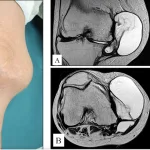

8時前に病棟に上がって, 昨日尺骨神経の神経鞘腫を核出した患者さんの病室を訪問.

手の力は正常に入り, 運動麻痺はありませんでしたが, 小指側のしびれ感があり.

末梢神経障害治療薬メチコバールを処方しました.

キズからの出血はほぼなく, 午後に退院することに.